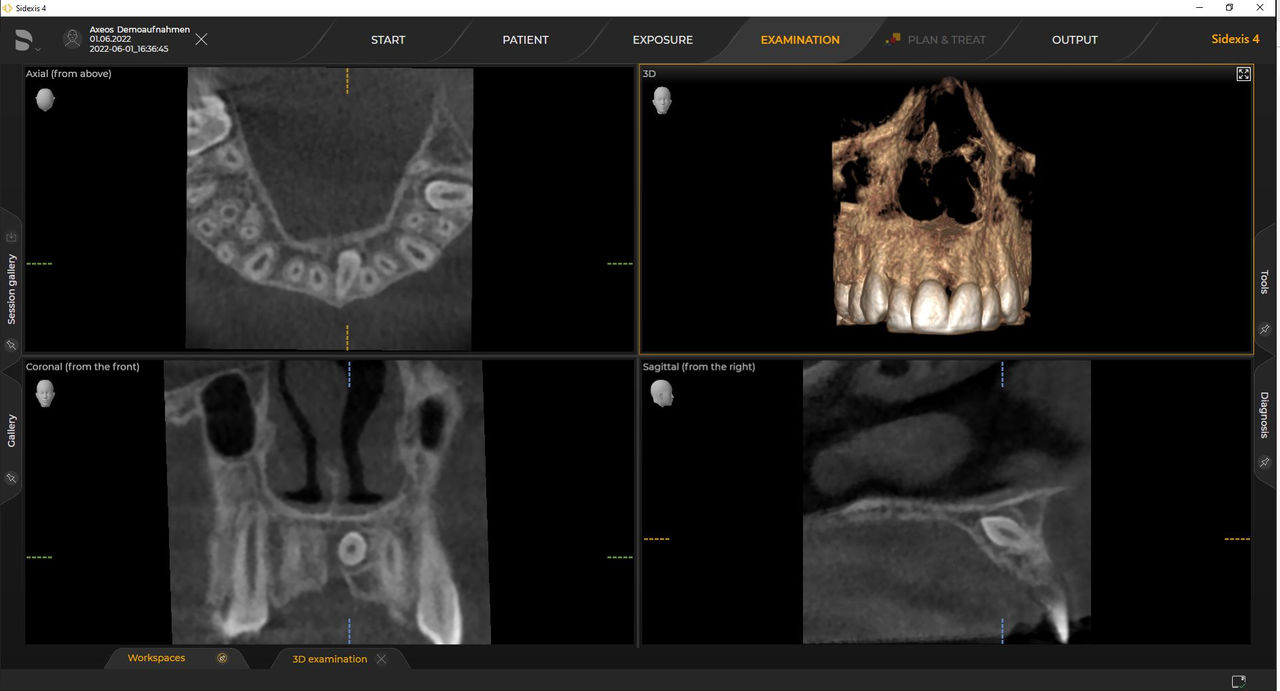

Los numerosos tamaños de volumen garantizan la flexibilidad en la práctica diaria. Examine un área precisa o evalúe la dentición completa, lo que incluye las ATM

Con el modo de dosis baja inteligente, obtiene radiografías 3D en el rango de dosis de una 2D. En el modo HD (hasta 1400), las imágenes individuales se obtienen durante una única rotación y se convierten en un volumen 3D con hasta 80 μm para imágenes de bajo ruido en alta resolución

Las unidades 3D de Dentsply Sirona funcionan exclusivamente con Sidexis 4. Sin embargo, la migración de datos de Sidexis XG a Sidexis 4 es muy fácil. Sidexis 4 permite una experiencia digital completa con las últimas herramientas.